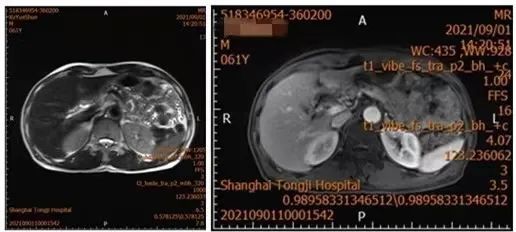

本例患者因上腹部間斷性鈍痛半年,在江西診斷胰腺佔位,特地來到同濟醫院找葛步軍主任進行手術治療。入院後進一步檢查考慮胰腺中段多發導管內乳頭狀粘液瘤,完善術前檢查後,於9月8日曆經3個多小時,完整切除術腫瘤,順利完成手術。

多髮乳頭狀粘液瘤(IPMN)可能

病理提示良性,出院後無後續治療